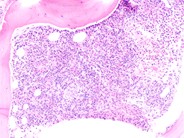

This is a bone marrow aspirate image showing macrophage phagocytosing a neutrophil with giant coarse granules characteristic feature of chediak higashi syndrome